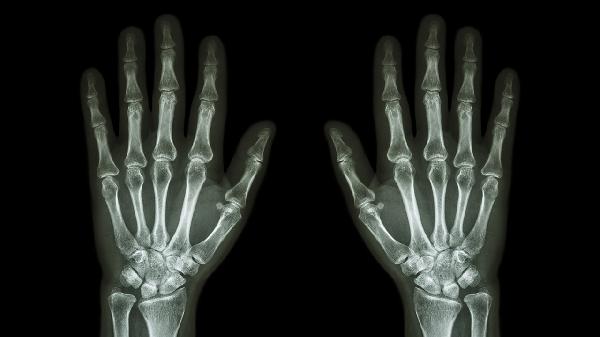

类风湿关节炎是一种慢性自身免疫性疾病,主要侵犯手足小关节。典型症状为晨僵持续超过1小时,关节呈对称性肿胀。可能与遗传、感染等因素有关。确诊后需长期使用甲氨蝶呤片、来氟米特片、艾拉莫德片等抗风湿药物。早期干预有助于延缓关节畸形。

骨关节炎属于退行性关节病变,多见于中老年人。关节软骨磨损导致骨赘形成,引发疼痛和活动受限。手指远端指间关节受累时可能出现赫伯登结节。治疗可选用硫酸氨基葡萄糖胶囊、塞来昔布胶囊、玻璃酸钠注射液等,配合关节保护性锻炼。